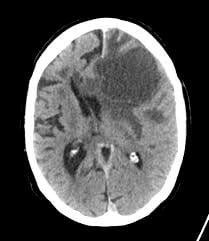

ung-thu-phoi-di-can-nao-1.jpg

Khối u di căn não.